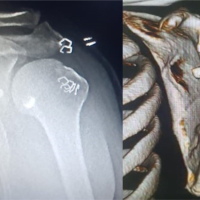

2 h after the accident, surgical treatment of the left four-part proximal humerus fracture was performed by minimally invasive plate osteosynthesis with a PHILOS® plate (Synthes; West Chester, USA). A central bone void was filled with an Allobone® allograft (Neutromedics AG; Charm, Switzerland) (Fig. 3c). An intra-operative diagnostic shoulder arthroscopy revealed no concomitant pathologies to the left shoulder joint, excluding any significant rotator-cuff injury, labral lesion, or chondral articular damage.